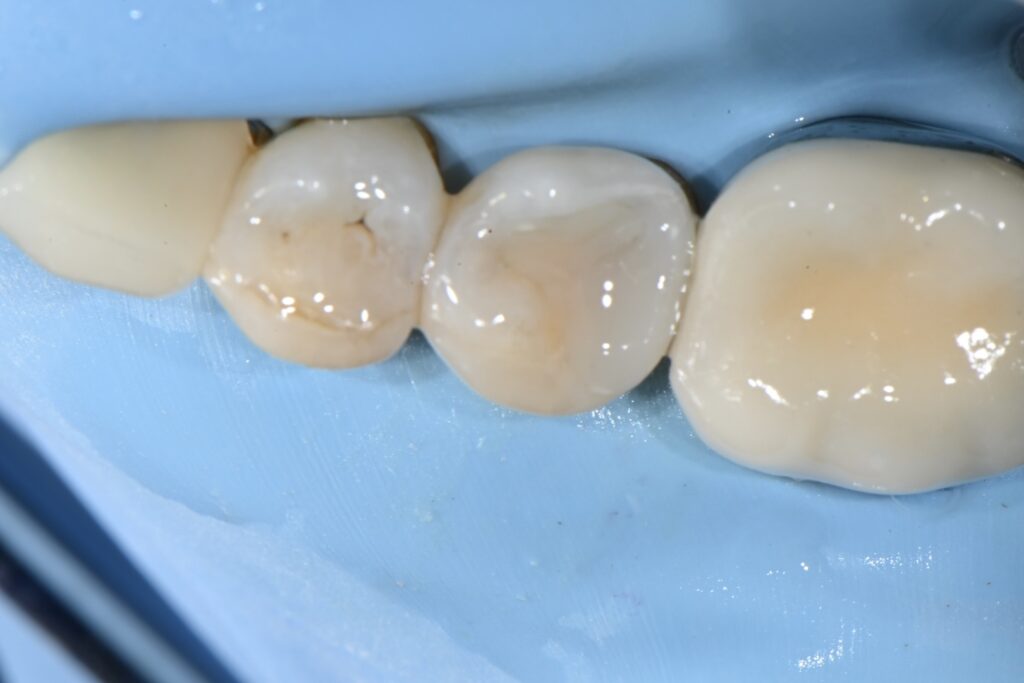

치아의 형태가 만들어져가고 있습니다

가장 큰 장점은 당일 완성 그리고 일상으로의 복귀 /신경치료의 가능성 줄어듬/자기치아의 삭제 최소화

이렇게 정의할 수 있습니다

당일 원데이 치료가 완료되었습니다

신경치료는 진행하지 않았고 1회의 진료로 완료되었으며

신경관과 근접하였지만 이차충치를 적절히 제거후

안전하게 치료가 마무리 된 것을 볼 수 있습니다.